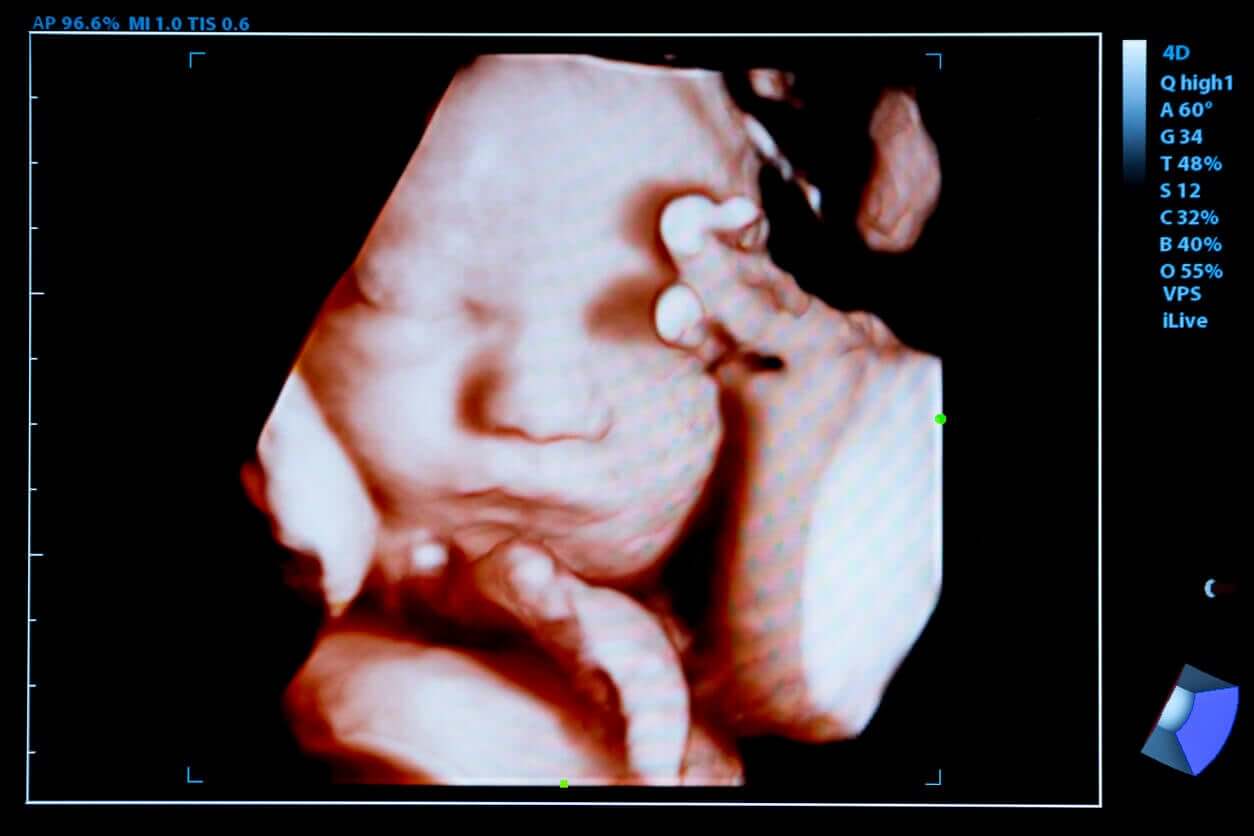

4. 3D og 4D ultralyd

Vi nevner disse to typene i en spesiell seksjon, på grunn av den store populariteten de har fått de siste årene, men utover muligheten de tilbyr å se babyens ansikt i detalj, diskuteres deres virkelige nytte av noen spesialister.

3- og 4-dimensjonale ultralyder gir bedre visualisering av fosteret og oppdager visse misdannelser, men dette betyr ikke at en tidlig diagnose av medfødte syndromer kan stilles. Flere verktøy er nødvendig for å bekrefte visse funn, og dette problemet er ikke så enkelt.

Generelt sett lar 3D-ultralyd deg få et tredimensjonalt bilde av fosteret, og 4D tilfører bevegelse til det. Gjennom sistnevnte er det mulig å se barnets liv mens det beveger seg inne i mors liv.